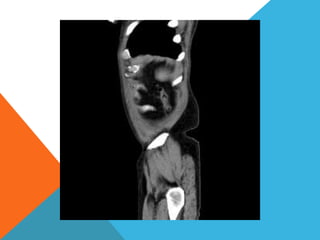

El paciente presentó síntomas de sangrado digestivo y pérdida de peso. Exámenes revelaron gastritis crónica asociada a H. pylori. Un tumor fue descubierto en una colonoscopia normal. La cirugía removió un tumor fibroide solitario, una rara neoplasia mesenquimal que usualmente crece lento y tiene bajo potencial de malignidad. El pronóstico después de la remoción quirúrgica es generalmente bueno.